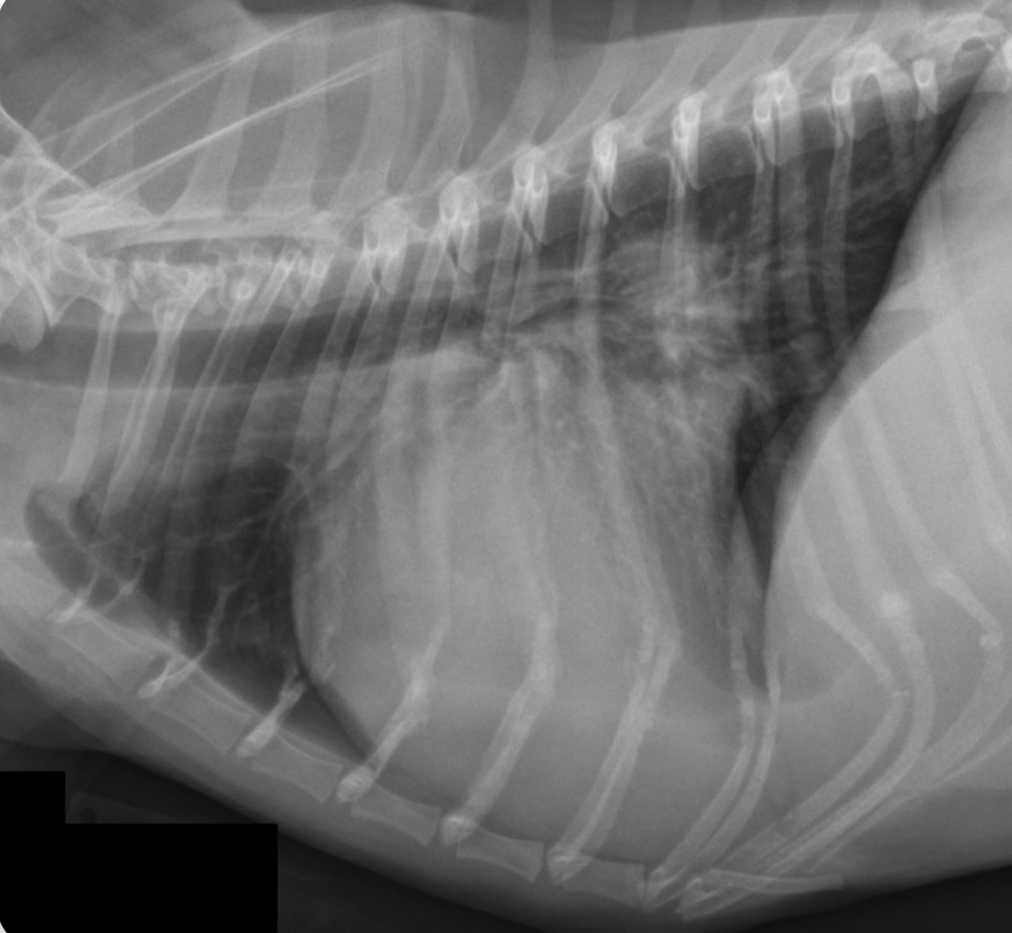

3 features of LAE on lateral

-dorsal displacement of main stem bronchi by a hunchback bump

-increased cd.dorsal cardiac border

-loss of cd.cardiac waist - straightening of cd.cardiac margin

3 features LVE on lateral

-tall heart (>2/3 DV diameter)

-dorsal displacement of trachea (almost parallel to spine)

-straightening of cd. border of heart

What part of the heart is enlarged?

LVE (technically LAE too) - prof used the same photo for both but outlined different features